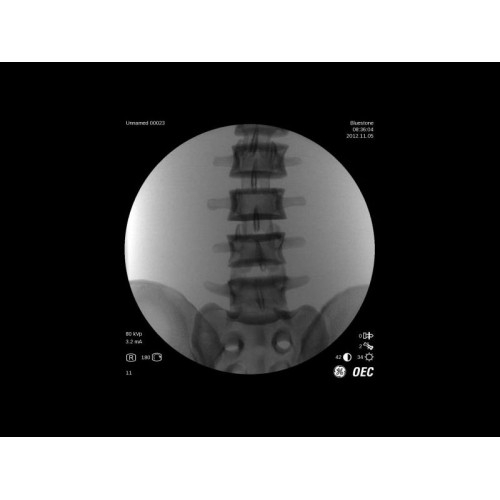

Передовая рентгенохирургическая система GE Brivo OEC 785/865 представляет собой современное решение для проведения малоинвазивных вмешательств под рентгенологическим контролем. Это оборудование нового поколения сочетает высокое качество визуализации с интуитивно понятным управлением, что делает его идеальным выбором для современных операционных.

GE Brivo OEC 785/865 оснащен инновационной системой обработки изображений, которая обеспечивает четкую визуализацию в реальном времени. Система автоматически адаптирует параметры исследования под конкретную хирургическую задачу, обеспечивая оптимальное соотношение качества изображения и лучевой нагрузки. Особое внимание уделено эргономике работы хирургической бригады.